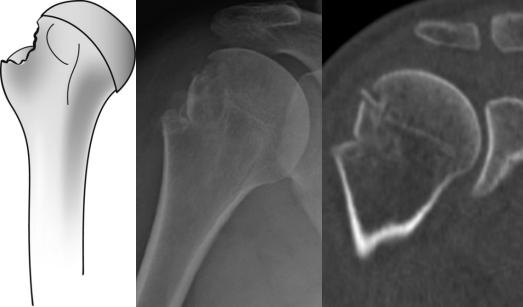

图8 大结节移位骨折的影像学与术中技术图示

常规腋位X线片(图a)及CT扫描(图b)显示肱骨大结节(GT)移位性骨折。术中可见冈上肌肌腱(SSP)及冈下肌肌腱骨性撕脱(图c)。采用双排经骨等效缝合桥技术固定骨折块:内侧排使用2枚缝合锚钉,外侧排应用2枚无结锚钉(图d)。术后X线显示腋位(图e)及前后位(图f)骨折解剖复位。

在处理向外侧延伸较远的骨折时,需特别注意外侧排锚钉的置入。由于视野受限以及三角肌下滑囊和骨膜组织的增生,锚钉可能被置入骨折线内。这可能导致初期植入物稳定性降低,并引发锚钉脱出等早期植入失败。为预防此并发症,强烈建议彻底清理三角肌下滑囊并充分显露下缘骨折线(图9)。

图9 术中照片显示大结节下缘骨折线。通过清晰显露大结节外侧面向下延伸的骨折线,可确保无结锚钉在缝线桥接结构中的安全置入。